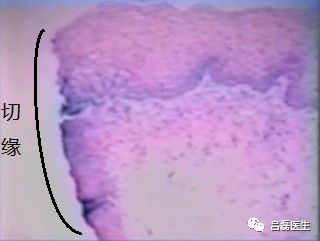

显微镜下观LEEP刀切缘(以上图片均来源于网络)

缺点是能量作用下切缘碳化,组织破坏,对病理科阅片可能会有影响。但也有不少报道认为,LEEP刀切除后的组织热灼伤很小,与激光手术相比,组织的切割边缘碳化很少,对活检影响不大。个人觉得,只要切缘距离病变范围足够,基本上没什么影响。